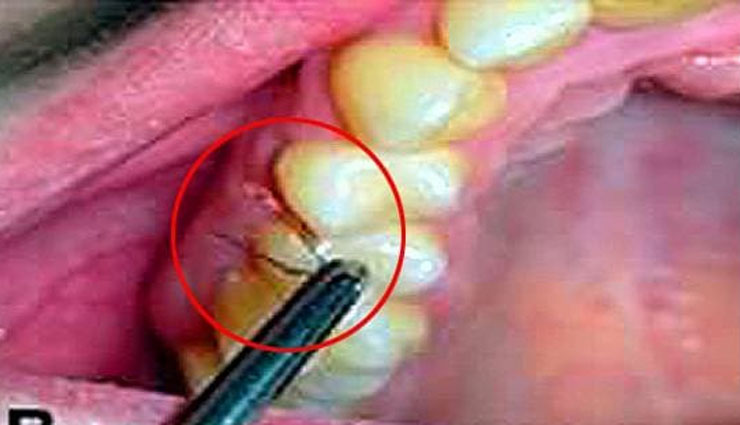

हमारे हाथ या पैर पर उगे बालों से हमें कोई परेशानी नहीं होती। लेकिन अगर हमारे मुंह में बाल उगने लग जाए तो हालत खराब हो जाती है। ऐसा ही कुछ हुआ इटली की एक महिला के साथ। महिला के मुंह में दांतों और मसूड़ों में बाल निकल रहे है। इटली की एक 25 वर्षीय युवती के मुंह में दांतों और मसूड़ों के बीच बाल उग आए हैं। दांतों और मसूड़ों ये एक बेहद दुर्लभ बायोलॉजिकल स्थिति है। इसे लेकर डॉक्टर भी हैरान हैं। डॉक्टरों के समझ में ये नहीं आ रहा है कि इसके पीछे कारण क्या है?

इटली के डॉक्टरों का मानना है कि इसके लिए पॉलीसिस्टिक ओवरी सिंड्रोम नामक दुर्लभ बीमारी जिम्मेदार हो सकती है। कुछ डॉक्टर इसे गिंगिवल हर्सुटिज्म (Gingival Hirsutism) बीमारी भी बता रहे हैं। इसमें शरीर के ऐसे हिस्सों में बाल उग आते हैं जहां नहीं होने चाहिए। हालांकि अभी तक इसका सही कारण डॉक्टर पता नहीं कर पाए हैं।

इटली की जिस महिला के मुंह के अंदर दांतों और मसूड़ों में बाल निकले हैं उसे 15 साल की उम्र में टेस्टोस्टेरोन ज्यादा होने की दिक्कत सामने आई थी। लेकिन उसका इलाज हो चुका है। डॉक्टरों ने अब उसके मसूड़ों के के ऊतकों की जांच भी की लेकिन कोई कारण पता नहीं चल पा रहा है।

यह पहली बार है जब किसी महिला को यह बीमारी हुई है। इसके पहले दुनिया में इस बीमारी से ग्रसित पांच पुरुष ही हैं। इन पुरुषों के मुंह के अंदर दांतों और मसूड़ों के बीच भी बाल उग आए थे।

डॉक्टरों का अभी तक यही मानना है कि यह महिला गिंगिवल हर्सुटिज्म से पीड़ित है। इस बीमारी और इससे पीड़ित लोगों के बारे में एक विशेष रिसर्च रिपोर्ट ओरल पैथोलॉजी जनरल में हाल ही में प्रकाशित हुई है।